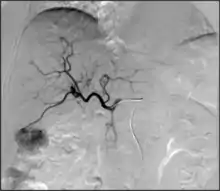

- Visceral Aneurysm affect the vessels that supply the solid organs. Similar to other aneurysms, treatment depends on several factors including size, location, shape and growth. Endovascular treatments for visceral aneurysms can usually be performed with less morbidity when compared to open surgical techniques.